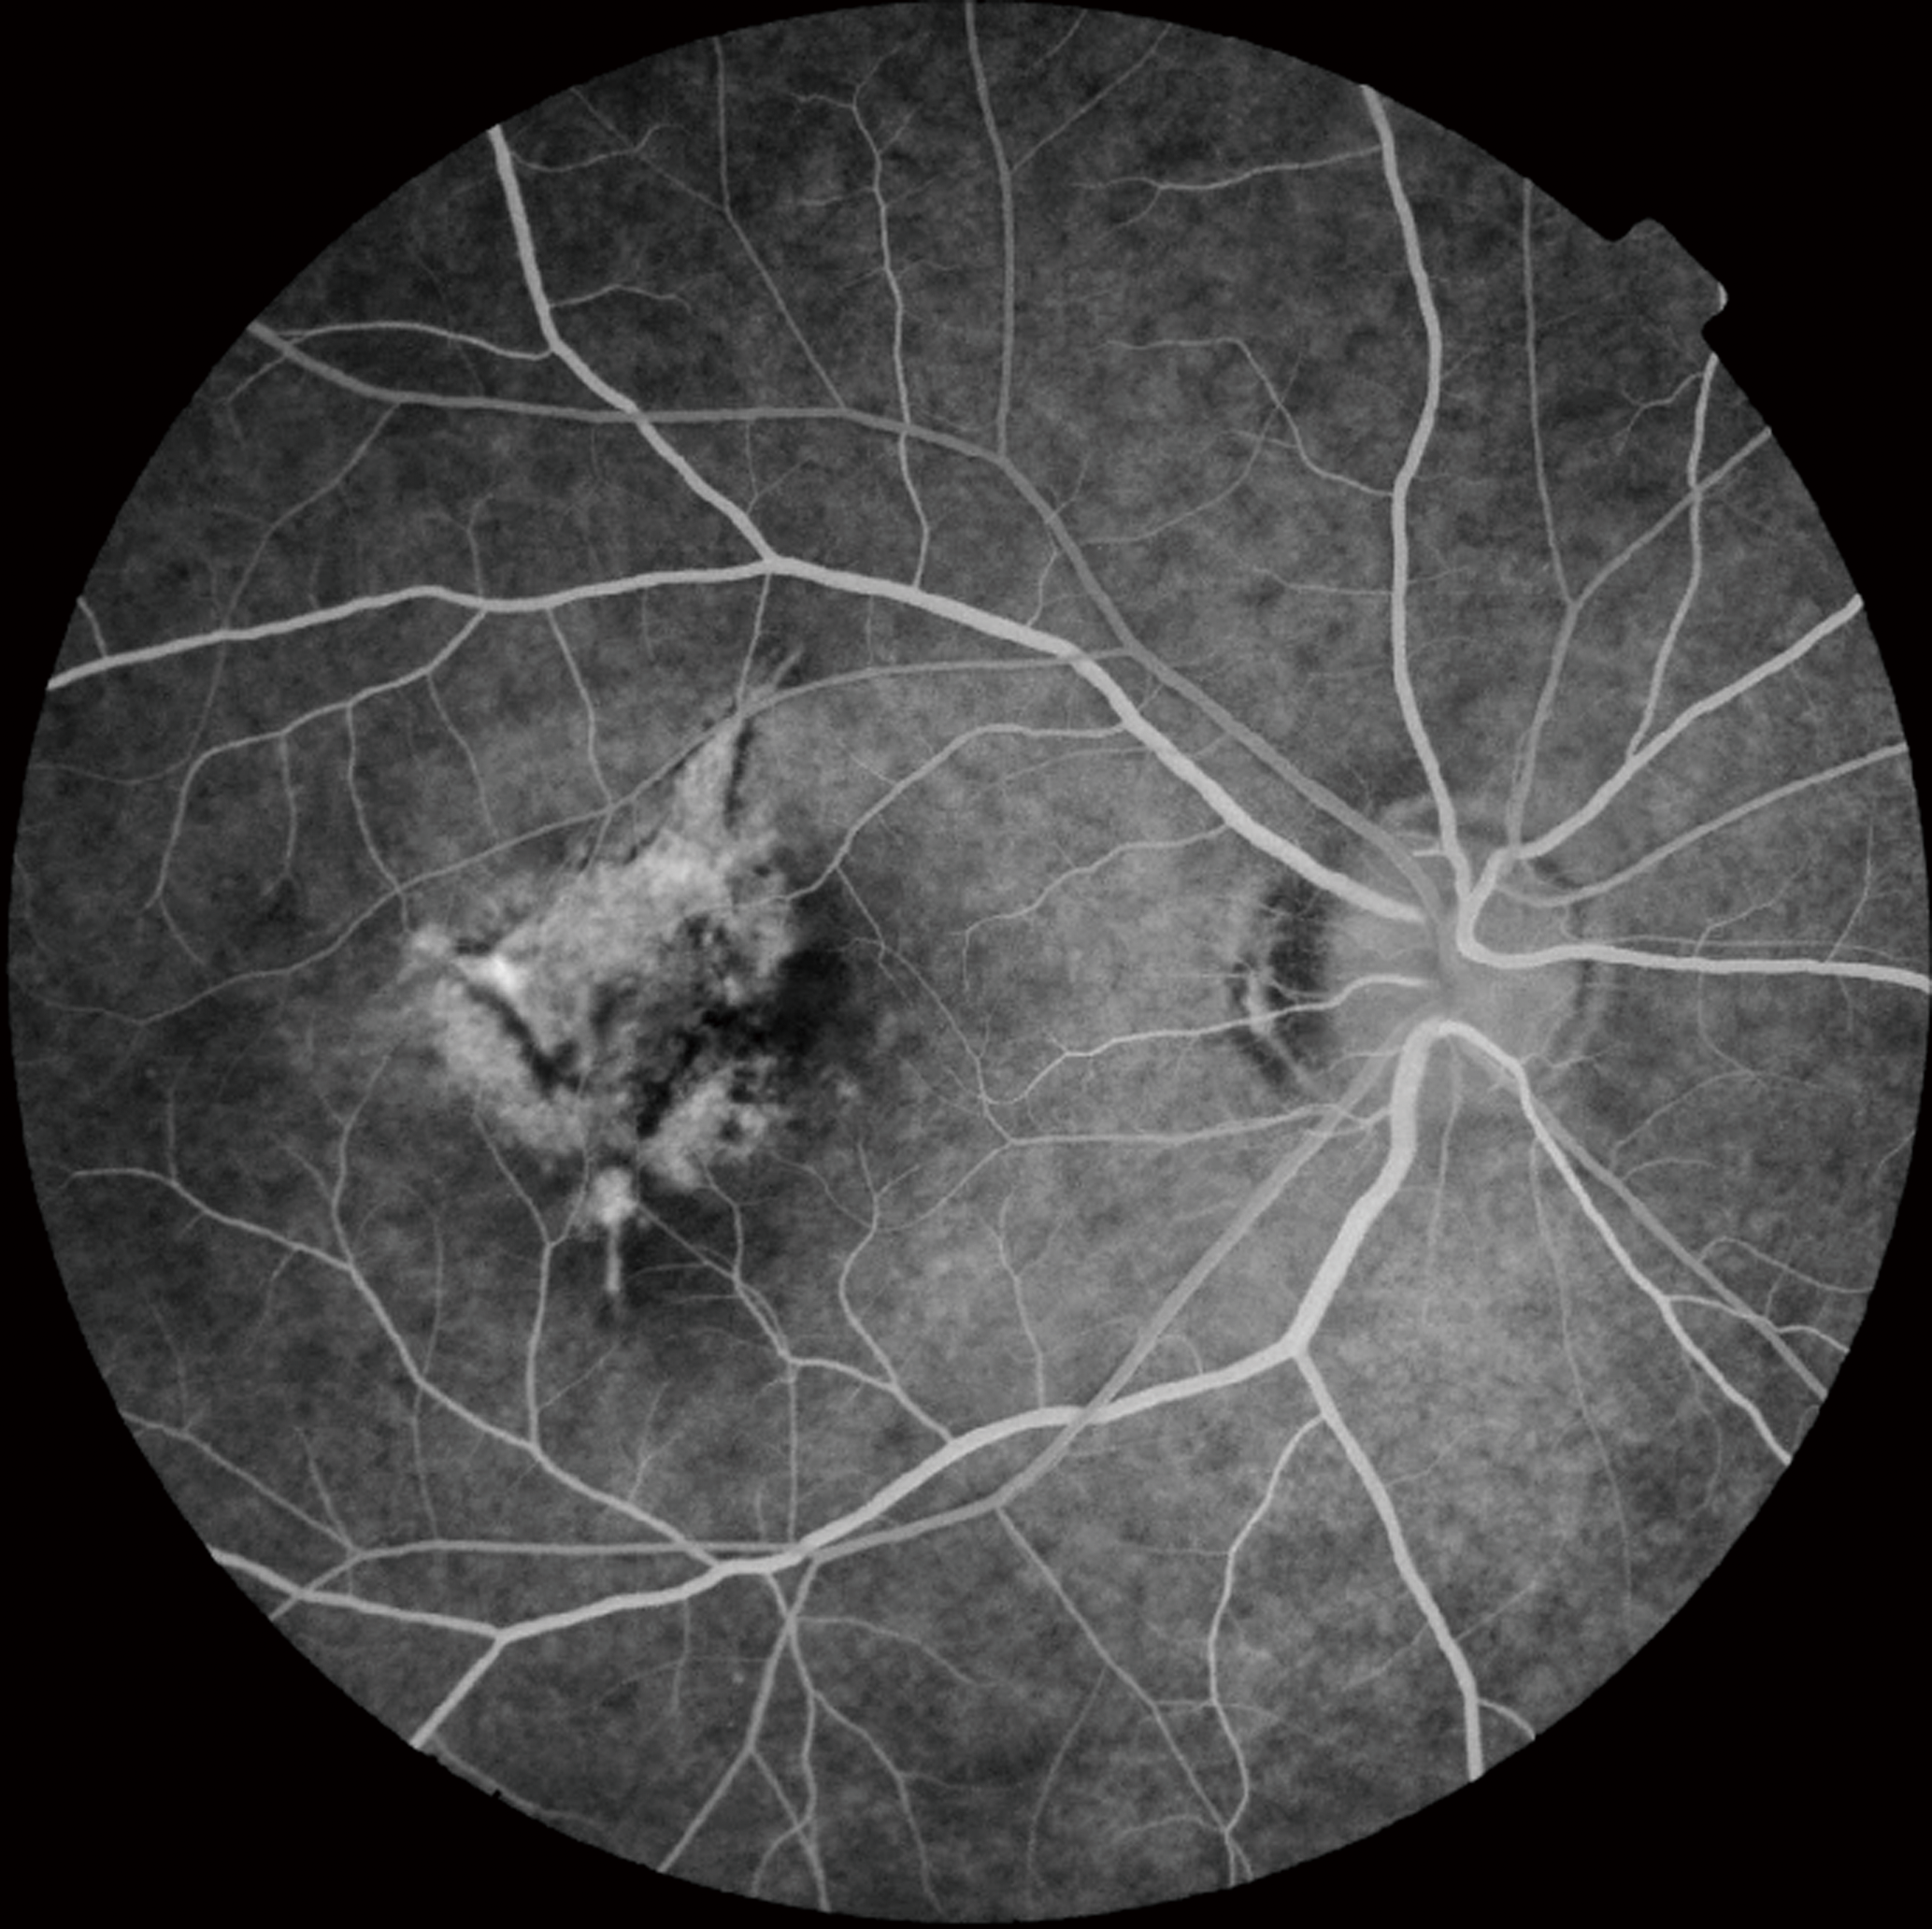

With TRC-NW8 series, it is possible to capture non mydriatic color, red-free and fluorescein angiography to answer all your many needs.